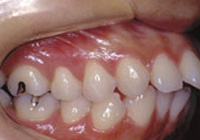

症例4:上顎前突(出っ歯)

治療前

治療後